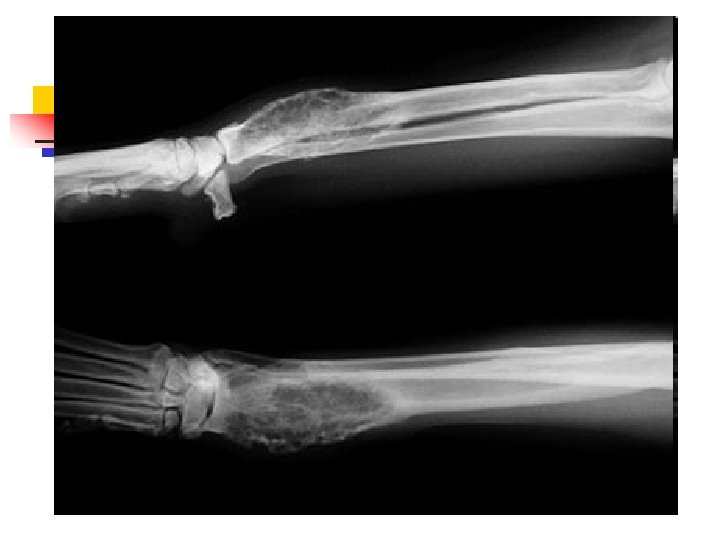

When Lameness isn’t Simple n n Sometimes when an animal limps the cause turns out to be something more serious than a simple injury. The doctors palpated a firm, painful lump in the leg this dog was favoring. Radiographs showed that the bone was expanded in that area, with a motheaten, hollowed-out center. These are classic signs of a tumor in the bone, known as an osteosarcoma.